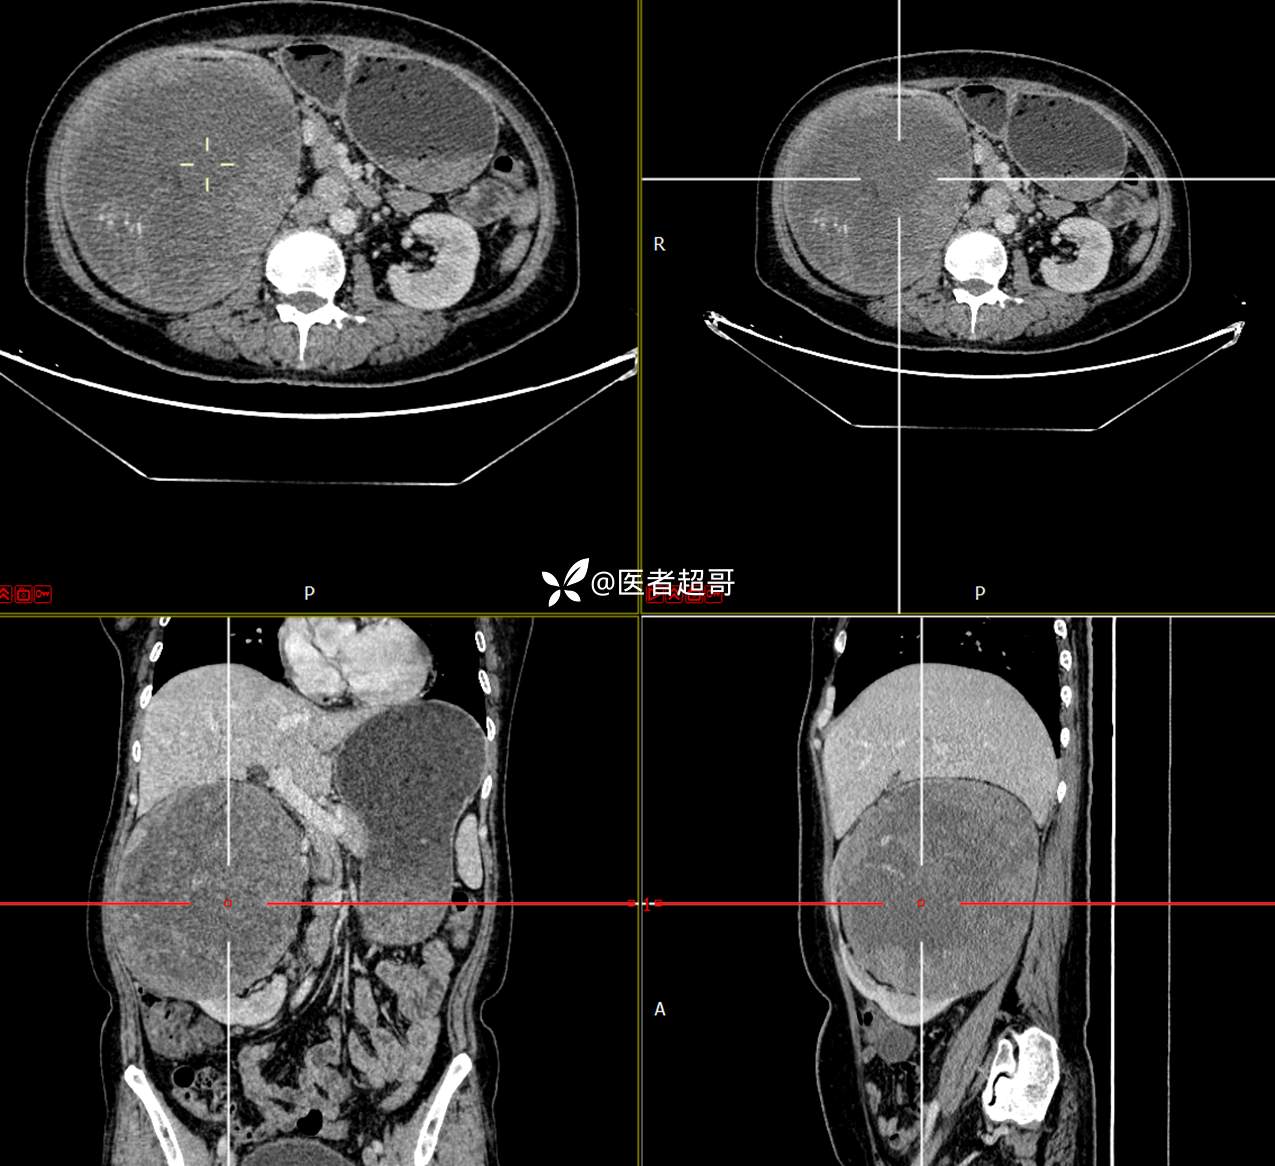

现病史:患者1周余前发现右上腹有一半球形巨大肿物,约18cm*15cm大小,既往贫血病史3年余,诉乏力,易疲劳,偶有头晕,活动后心悸,无腹痛、腹胀,无恶心、呕吐,无尿频、尿急、尿痛,无排尿困难,患者为求进一步治疗,来我院消化内科就诊,门诊行肝.胆.胰.脾.肾彩超示:右肾上部囊实性占位,范围约18.0cm×11.7cm×16.4cm,边界清,形态规则,建议进一步检查,腹膜后实性结节。我科遂以“肾肿物”收治入院,患者自发病以来,神志清、精神可,睡眠、饮食可,二便正常,体重、体力略有下降。